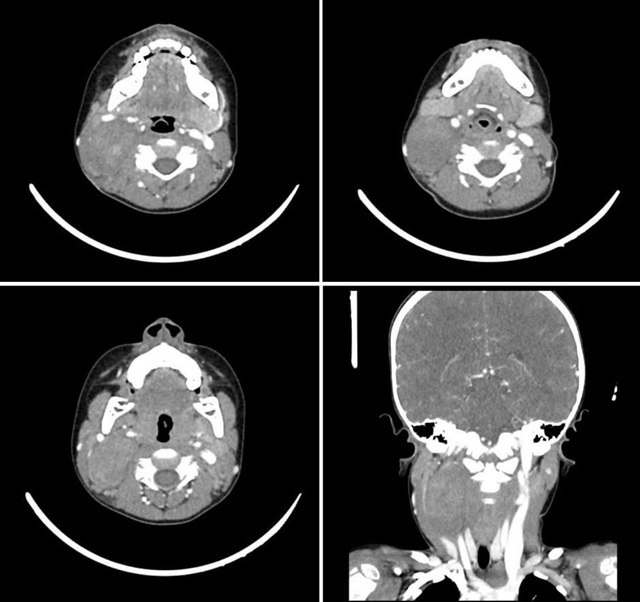

Contrast-enhanced CT and MRI imaging of the neck revealed a large, well-defined isodense area seen in the posterior right neck, measuring 57 x 35 x 30 mm, showing heterogeneous contrast enhancement. The lesion contained foci of calcification and demonstrated increased vascularity, with imaging features highly suggestive of a paraganglioma (Figure 1). Multiple enlarged but benign-appearing lymph nodes were also noted at levels II and III on the right side. The lesion caused splaying of the external and internal branches of the right common carotid artery and compression of the internal jugular vein (IJV). It exhibited an isointense signal on T1- and T2-weighted sequences with homogeneous intense enhancement on post-contrast sequences.

Figure 1 – CT Scan imaging